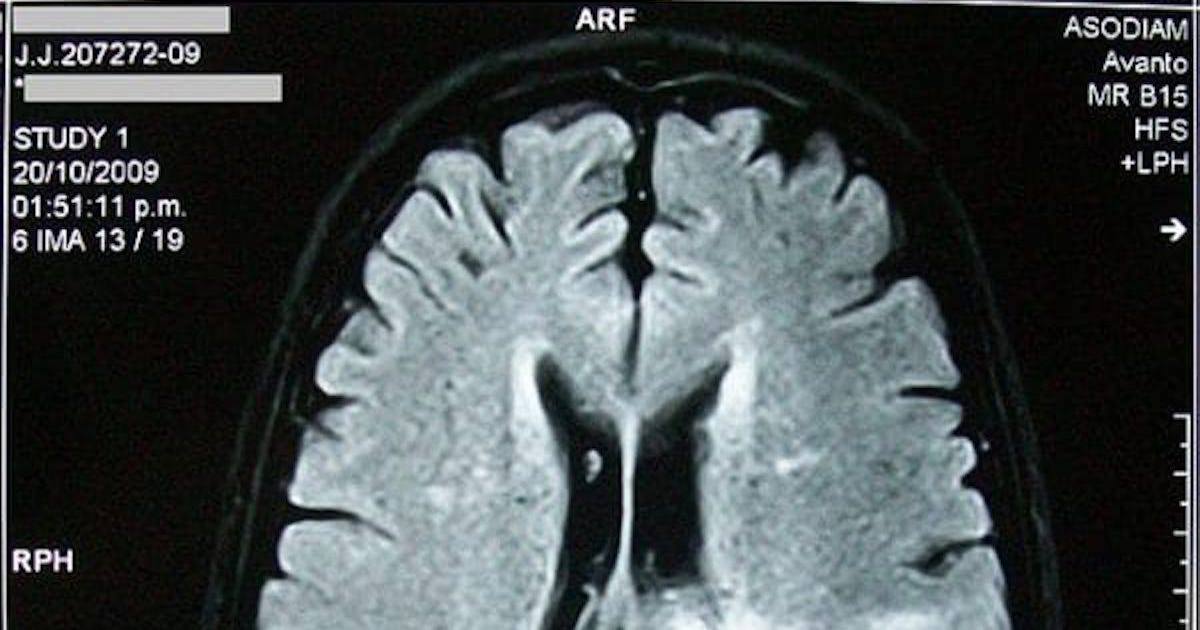

למעשה, החלק של המוח שמאחסן את הזיכרונות גם כותב זיכרונות חשובים על חשבון זיכרונות ישנים ולא חשובים.

אבל האינטליגנציה של המוח השוכח לא מסתיימת שם. היא גם עוזרת לנו למיין זיכרונות ישנים שאנחנו כבר לא צריכים, כדי שיהיה לנו מקום לזיכרונות חדשים וחשובים יותר.